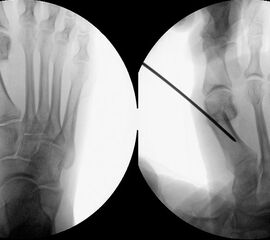

Präoperatives Röntgenbild Fuß d.p. mit eingezeichneten Winkeln. A) Intermetatarsalwinkel, B) Hallux valgus Winkel, C) Interphalangeal-Winkel.

Abbildung 2

• Operationsplanung anhand der Röntgenaufnahmen unter Beachtung wichtiger radiologischer Landmarks wie Intermetatarsalwinkel, Hallux valgus – Winkel, distaler Gelenkflächenwinkel (Distal Metatarsal Articular Angulation - DMAA), Metatarsaleindex und Sesambeinposition (Abb. 2).